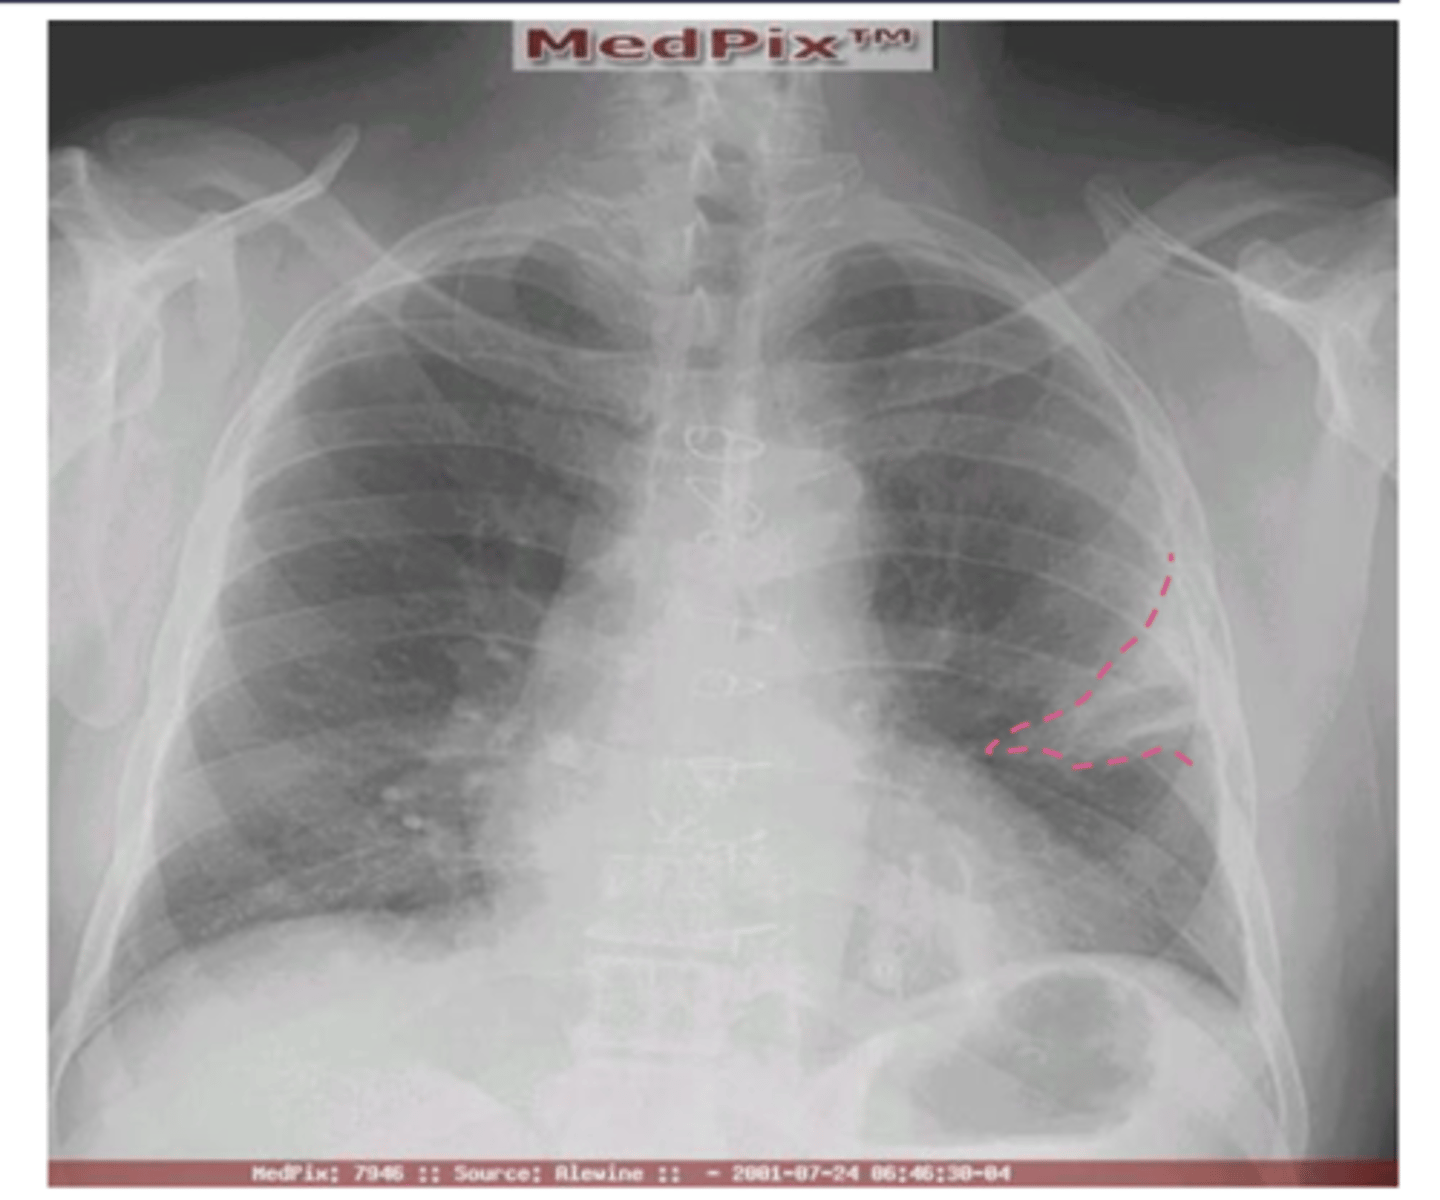

What is hampton's hump?

Wedge shaped pleural based opacity --> indicative of pulmonary embolism

<p>Wedge shaped pleural based opacity --&gt; indicative of pulmonary embolism</p>